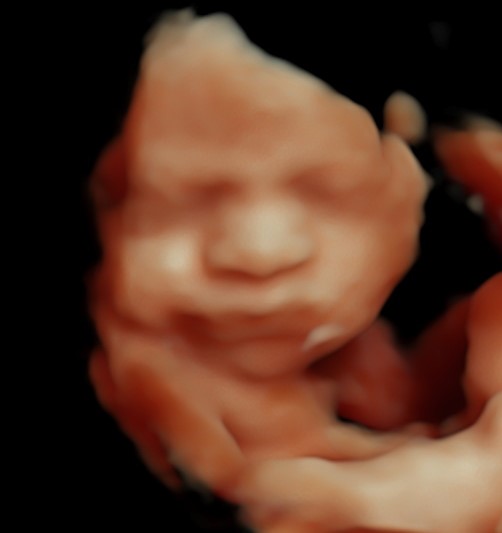

4D/5D/HD Ultrasound Gallery

Gallery